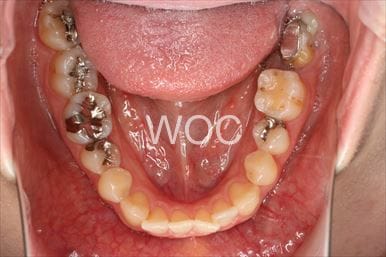

八重歯・叢生エッジワイズ装置

特に装置の希望はなかったので、エッジワイズ装置を選択。

ガタガタは強いが非抜歯治療を選択。定期的通院に協力的なため、予定より短い期間で終わることができました。-

- 年齢:24歳女性

- 主訴:上下前歯のガタガタが気になる

- 基本矯正料金:80万円

- 治療期間:1年5ヶ月

- 非抜歯